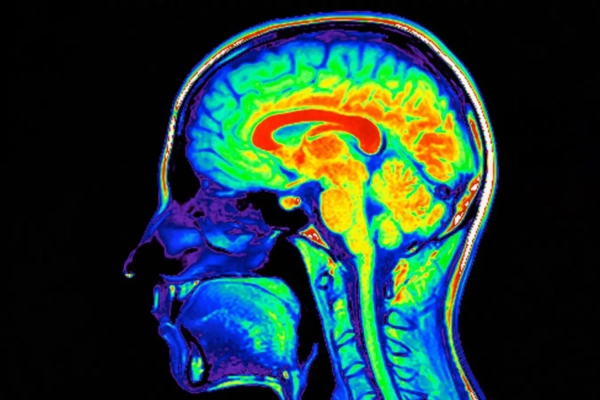

Ультразвуковые волны могут проникать через череп в мозг Shutterstock/peterschreiber.media